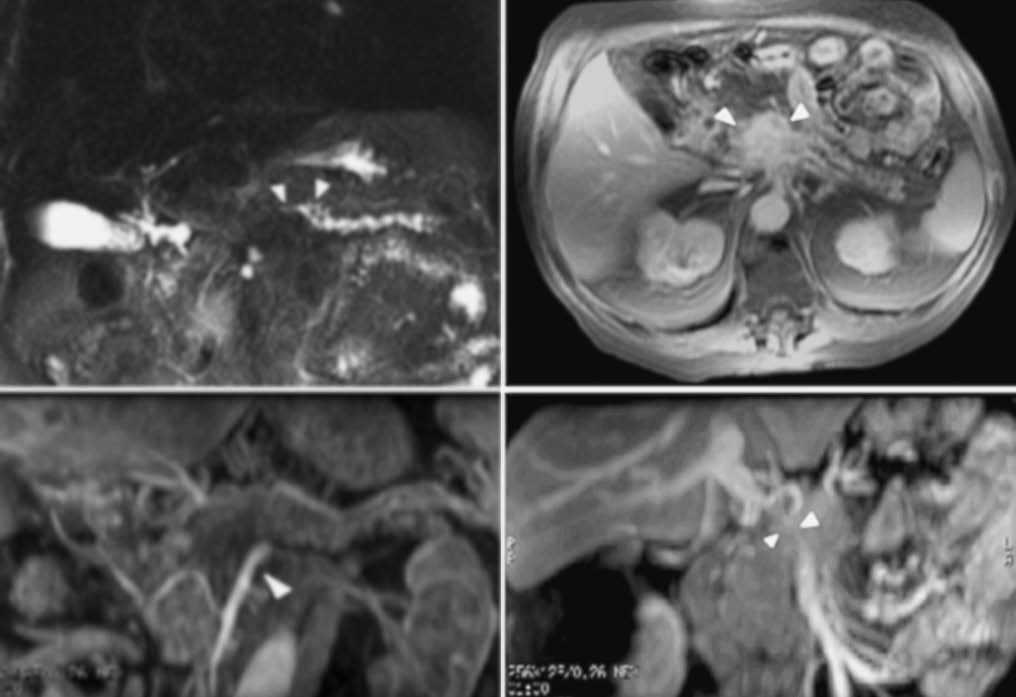

López Hänninen et al53, utilizando RM dinámica y CPRM, definen un valor predictivo positivo y negativo para neoplasia irresecable pancreática del 90 y 83% respectivamente, una sensibilidad y especificidad del 69 y 95% y un rendimiento global del 85%. Fischer et al54 presentan un valor predictivo positivo de la RM del 87% para la resecabilidad tumoral local cuando seleccionan sólo los tumores sólidos de su serie, que fueron 29 casos. Los autores definen esta técnica como la de mayor coste-eficacia y la proponen como la única a realizar en el diagnóstico de extensión del cáncer (fig. 12) de páncreas basándose en la política de «todo en uno»: toda la información requerida obtenida en una sola técnica diagnóstica.

Fig. 12.--Neoplasia irresecable de cuerpo pancreático. (A) Colangiorresonancia magnética que muestra una dilatación del conducto de Wirsung al nivel de la cola pancreática con stop brusco al nivel del cuerpo (puntas de flecha). (B) secuencia de resonancia magnética potenciada en T1 con saturación grasa tras la administración de contraste endovenoso. Masa heterogénea a nivel del cuerpo pancreático (puntas de flecha) que dilata el conducto de Wirsung. (C) angiorresonancia magnética en fase arterial. Se observa la arteria mesentérica superior permeable, pero ampliamente rodeada por el tumor pancreático (punta de flecha). (D) angiorresonancia magnética en fase venosa con estenosis severa del confluente porto-mesentérico (puntas de flecha).